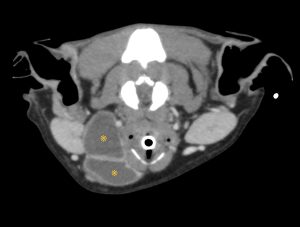

唾液は、唾液腺(下顎腺、舌下腺、頬骨腺、耳下腺)で作られ、導管を通って口の中に流れる消化液です。唾液瘤は、なんらかの原因による導管の損傷により唾液が周囲に漏出する疾患です。通常は無症状ですが、部位によっては気道を圧迫したり、飲み込みづらくなったり、感染から敗血症になる事もあります。

今回のワンちゃんは、CT検査で舌下腺との連続性が確認できたため、下顎腺と舌下腺と導管を切除しました。導管は顎舌骨筋を切開したり、舌神経をくぐらせたり、可能な限り先端まで切除しました。できるだけ先端まで切除することで、再発を防ぐ事ができます。